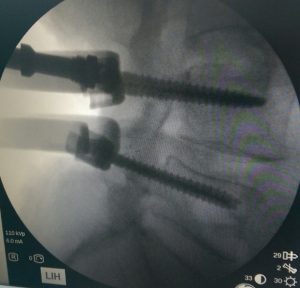

Para lograr una fijación adecuada durante la artrodesis, es habitual recurrir al uso de diversos tipos de implantes quirúrgicos. Entre los más utilizados se encuentran los tornillos, las barras metálicas, las cajas intersomáticas y las placas, etc. Todos estos elementos cumplen una función clave: mantener la correcta alineación de los segmentos vertebrales mientras se produce la fusión ósea, ofreciendo así una estructura sólida y estable.

foto de intervención de artrodesis